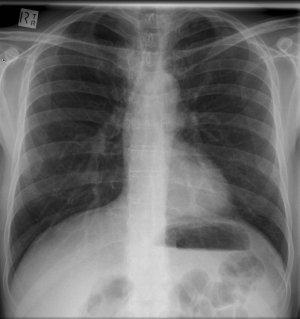

Until the early 1980s, patients were exposed to minuscule amounts of radiation from basic X-rays, for example, mammograms (0.4 mSv), chest X-rays (two views, 0.1 mSv) and dental X-rays (0.005 mSv)